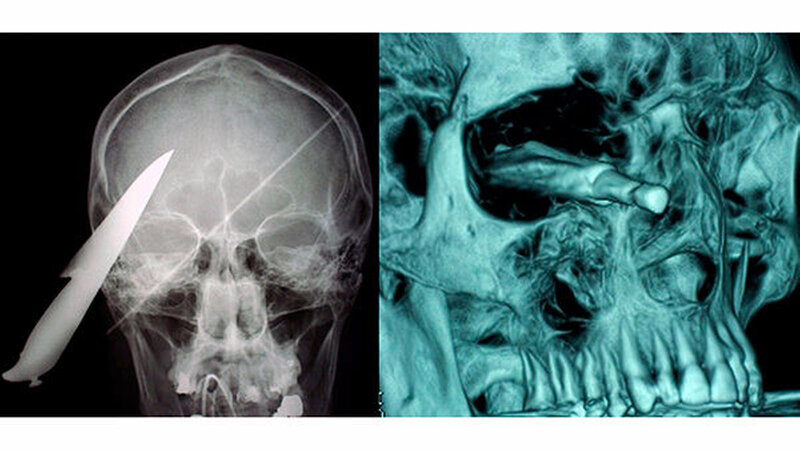

Vom Bohrer im Kopf bis zum Schlüssel in der Kieferhöhle: Die MKG-Chirurgen der Charité haben ausgewählte Patientenfälle mit Fremdkörpern im Gesicht zusammengestellt. In unserer Fotostrecke finden Sie die eindrucksvollen Aufnahmen.